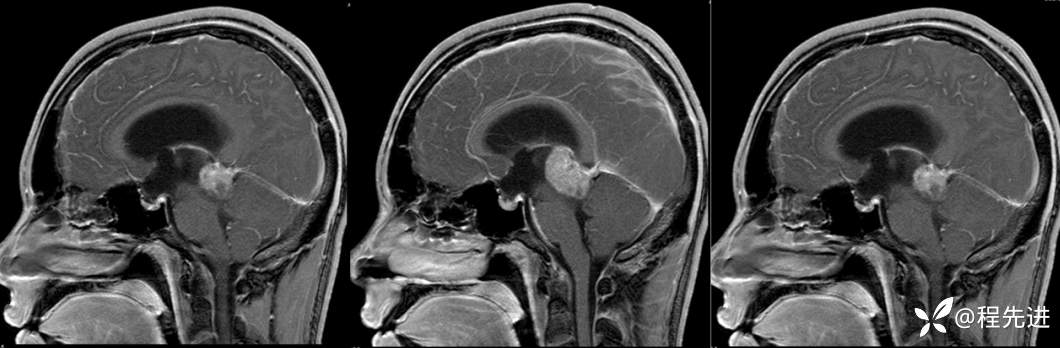

MRI平扫+增强:

T1增强: